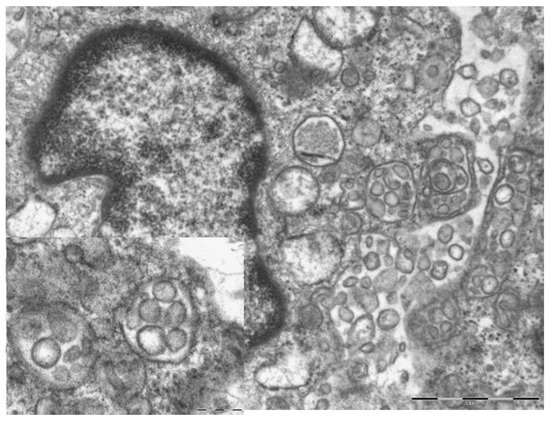

3.1. Erythema-Multiforme Like Eruptions

3.2. Pseudochildblains